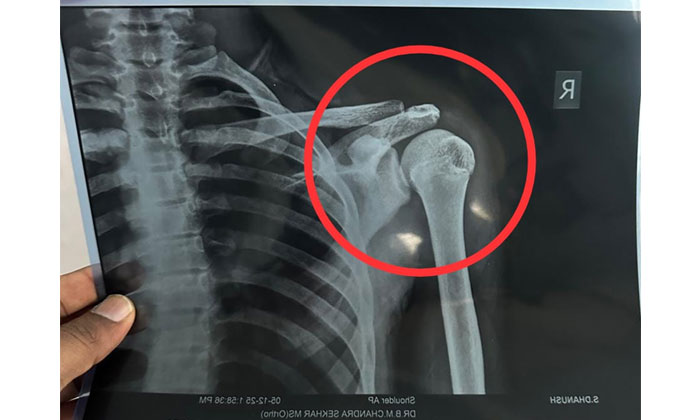

- 10వ తరగతి విద్యార్థి ధనుష్కు విరిగిన భుజం ఎముక.

అయితే, ధనుష్ పరిస్థితి విషమిస్తున్నట్లు గమనించిన తల్లిదండ్రులు అతన్ని ఆసుపత్రికి తరలించగా, వైద్యులు భుజం ఎముక విరిగినట్లు నిర్ధారించారు. కనీసం నెలరోజులు పూర్తిగా విశ్రాంతి అవసరమని సూచించారు. ఈ సంఘటనతో తల్లిదండ్రులు స్కూల్ యాజమాన్యం పట్ల తీవ్రమైన ఆగ్రహం వ్యక్తం చేస్తున్నారు. విద్యార్థుల భద్రతకు తగిన చర్యలు తీసుకోవడంలో స్కూల్ వైఫల్యం ఉందని వారు ఆరోపిస్తున్నారు.